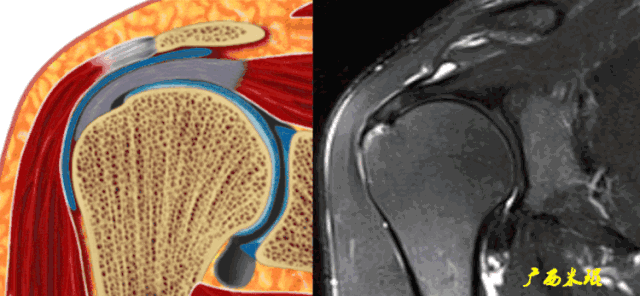

正常肩袖的MRI表现

各个序列肩袖均表现为均匀的低信号,是肌腱的延续。

肩袖损伤的MRI分级(Zlaikin)

Grade0:肩袖形态正常,连续性完好,肩袖信号正常。

Grade1:肩袖形态正常,连续性完好,肩袖内信号异常。

Grade2:肩袖连续性存在,形态异常(肩袖变薄/变厚,形态不规则)。

Grade3:肩袖外形异常,连续性中断。

在Zlaikin分级中,0级是正常肩袖,1、2级代表退变,3级为撕裂,也就是真正的肩袖损伤。